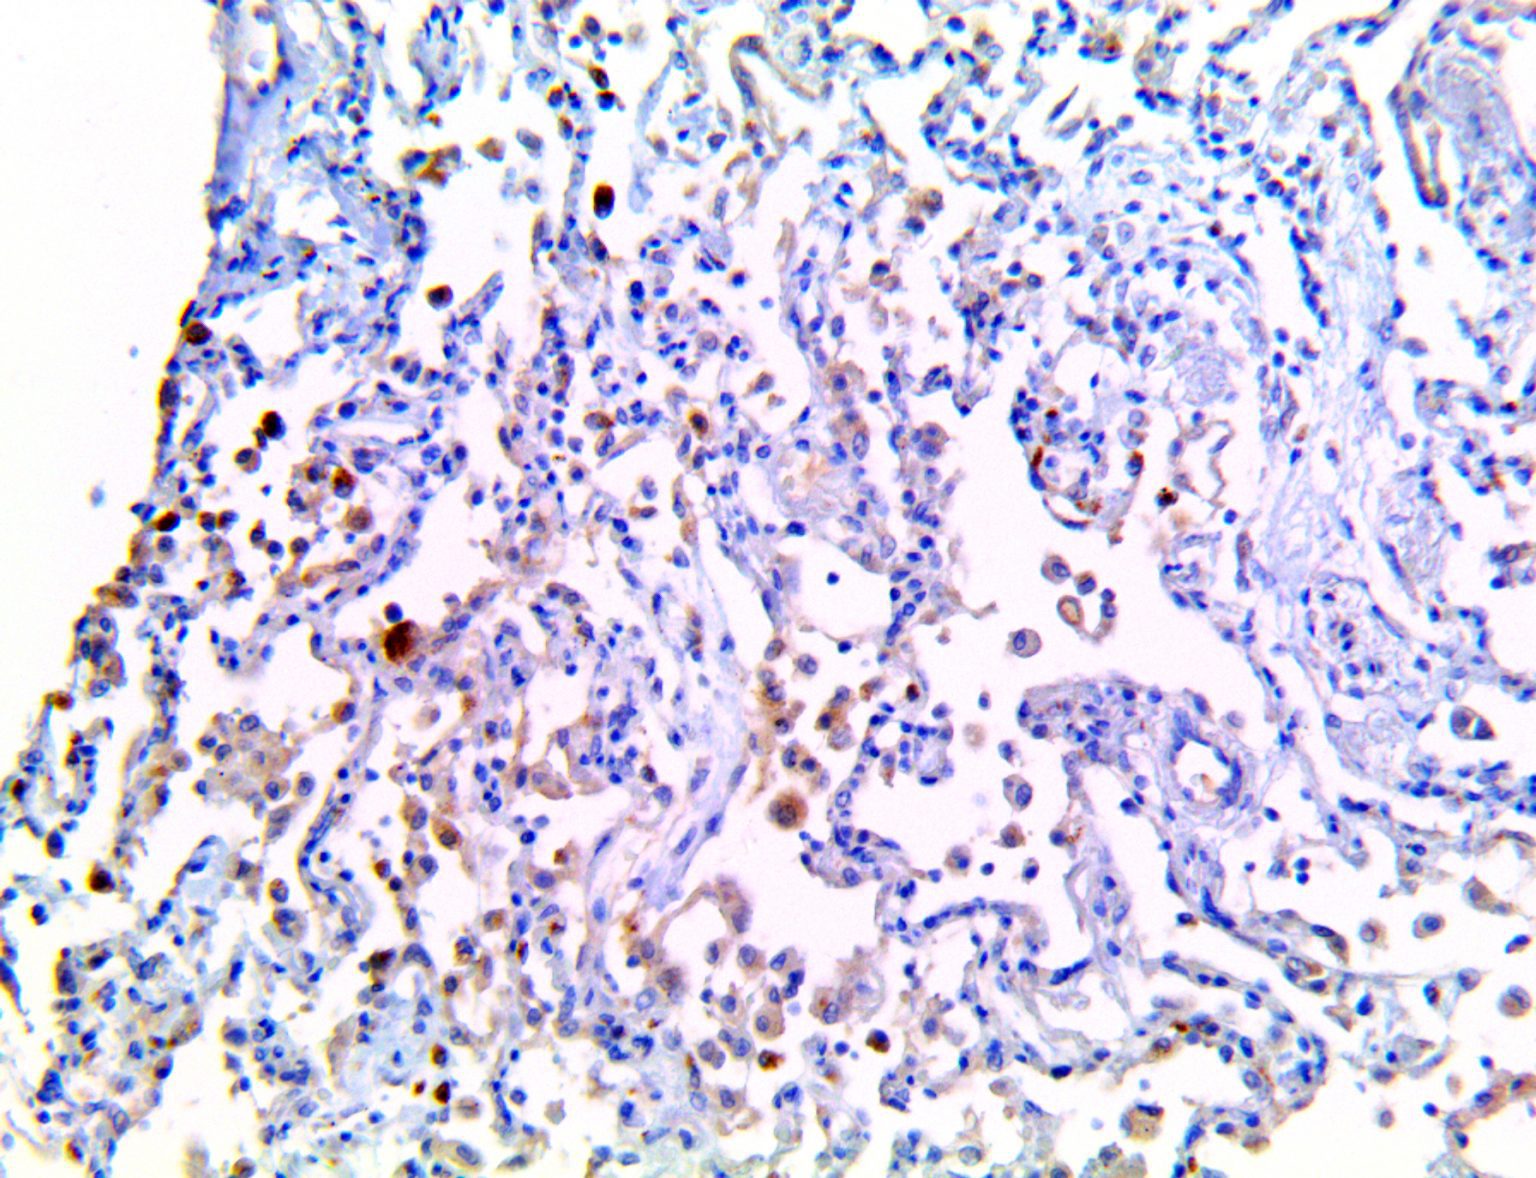

The vast majority of patients with COVID-19 have had a good prognosis, but there are still some critical individuals and even death.10 Most of these critically ill and dead patients do not develop severe clinical manifestations in the early stages of the disease. Some patients only show mild fever, cough, or muscle soreness. These conditions suddenly deteriorate in the later stages of the disease or in the recovery process . Acute respiratory distress syndrome (ARDS) and multiple-organ failure occur rapidly, resulting in death within a short time. Cytokine storm is considered to be one of the major causes of ARDS and multiple organ failure.

It is the ICU physician who is most likely to witness one of the deadliest manifestations of the abnormal immunological response, the cytokine storm syndrome (CSS). This response is also referred to by some as the cytokine release syndrome (CRS). CSS is characterized by continuous activation and expansion of macrophage and lymphocyte populations, which secrete large amounts of cytokines, causing the cytokine storm. This massive cytokine release is akin to hemophagocytic lymphohistiocytosis (HLH) disease, a syndrome characterized by initial unchecked and persistent activation of cytotoxic T lymphocytes and NK cells.

This activation induces inflammatory monocytes to highly express IL-6, starting a localized and then systemic cascade effect that results in hyperproduction of IL-6, which accelerates the inflammatory process. Because IL-6 also increases vascular permeability, excessive levels cause blood vessels to become very leaky. This, along with clotting factors released from vascular endothelial cells, stimulates the coagulation cascade, resulting in microthrombosis (tiny clots), which leads to ischemia and tissue death of the kidney, intestines, heart, liver, brain and extremities.